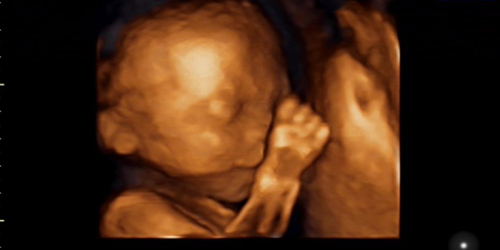

据介绍,二维超声就是老百姓所说的普通B超检查,也叫实时超声、灰阶超声,其显示的是二维切面图像,而三维、四维显示的是立体图像,看起来可能会更加直观。“三维、四维是最近几年发展起来的一种成像技术,目前临床上应用在基础研究多一些,但如果独立用三维、四维超声做产前检查,还无法达到二维超声的效果。”涂长玉说。

在他看来,三维、四维超声在空间、时间以及分辨率方面还有致命的缺陷,但相对来说,上述两种超声也有一定的优势,比如立体的形态、内部结构的显示以及表面特征等方面比二维超声显示的图像更为直观一些,其对于疾病的定位、定量、定性等有一定的辅助作用。未来随着这方面研究的增多,三维、四维超声在产前超声检查中或许会有良好的应用前景。